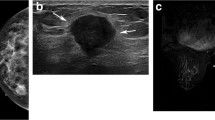

For CAD analysis, all MRI images were transferred to a commercially available CAD system (CADstream, Confirma Inc. Bellevue, WA). This workstation compared pixel intensity values on the precontrast and first contrast-enhanced series to classify enhancement. If the pixel value increased above a set enhancement threshold, CAD assigned a specific color to each pixel of tumors. If a pixel value of tumor did not increase by the established threshold, no color enhancement was made on the tumor. When the tumor above the set threshold had a presence of color overlay on the angio-map, CAD semi-automatically calculated tumor size using coronal, axial, and sagittal images and provided the three-plane measured sizes (Fig. 1). Some areas outside the breast such as blood vessels were also colored on the angio-map, but CAD was trained to accurately recognize the area of enhancement of the breast and did not include it in tumor size measurements. For CAD analysis, we applied 3 thresholds (30, 50, and 100%) which were most commonly used in clinical practice and acquired the tumor sizes calculated by CAD at each threshold (Figs. 2 and 3). Among three- plane measured sizes of tumors generated by CAD, we selected the longest tumor size.

MR images of a 54-year-old-woman with ductal carcinoma in situ. a Axial fat-suppressed dynamic contrast-enhanced T1-weighted image shows 43 mm-sized regionally distributed non-mass enhancement in the left middle-inner breast. b-d In the same image obtained with a computer-aided detection system, the non-mass enhancement indicated by the presence of color overlay was measured as 34 mm at the 30% threshold, 24 mm at the 50% threshold, and 21 mm at the 100% threshold. e Actual pathologic tumor size was 38 mm on gross specimen